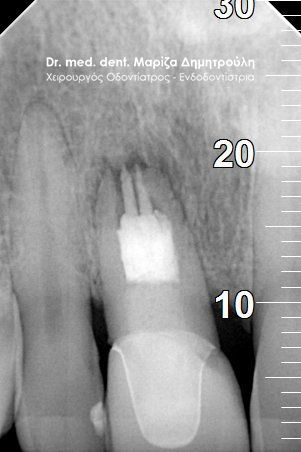

Η ασθενής προσήλθε στο ιατρείο με πόνο στον αριστερό πρώτο μόνιμο γομφίο. Πριν χρόνια είχε πραγματοποιηθεί στο συγκεκριμένο δόντι απονεύρωση από κάποιον οδοντίατρο. Παρόλ΄αυτά το δόντι τις τελευταίες εβδομάδες την πονούσε τόσο κατά τη μάσηση όσο και αιφνίδια χωρίς να υπάρχει κάποιο ερέθισμα.

Μετά τη λήψη ακτινογραφίας διαπιστώθηκε οτι οι δύο από τις τρεις ρίζες του δοντιού είχαν μία ατελή έμφραξη, η οποία δεν έφτανε ως το ακρορριζικό τρήμα του δοντιού. Κλινικά το δόντι πονούσε έντονα κατά την επίκρουση.

Σε συνεννόηση με την ασθενή αποφασίστηκε η επανάληψη της ενδοδοντικής θεραπείας (απονέυρωσης) και η αποκατάσταση του δοντιού με καινούριο λευκό σφράγισμα.

Μετά την χορήγηση τοπικής αναισθησίας τοποθετήθηκε ελαστικός απομονωτήρας (λάστιχο) και έγινε διάνοιξη του δοντιού. Στη συνέχεια ξεκίνησε η επανάληψη της ενδοδοντικής θεραπείας (απονεύρωση) με την αφαίρεση του παλιού εμφρακτικού υλικού σε όλο το μήκος των τριών ριζών του δοντιού. Ακολούθησε η επεξεργασία του δοντιού με μηχανοκίνητα εργαλεία και οι διακλυσμοί ( έκπλυση ) στο εσωτερικό των ριζών για την απομάκρυνση των νεκρών οδοντικών ιστών / κυττάρων και την απολύμανση των ριζών. Έγινε τοποθέτηση φαρμάκου και έγινε προγραμματισμός για τη συνέχιση της απονεύρωσης σε επόμενο ραντεβού.

Εφόσον η ασθενής δεν πονούσε και το δόντι ήταν ασυμπτωματικό, ακολούθησε η ολοκλήρωση της απονεύρωσης με της έμφραξη των ριζών του δοντιού καθώς και η αποκατάσταση του δοντιού με έμφραξη ρητίνης.

ΠΡΙΝ

ΜΕΤΑ